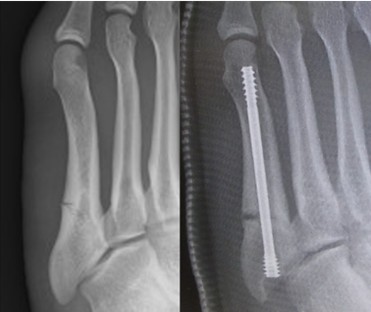

スポーツ外傷では疲労骨折が問題となることが多いです。様々な場所に生じる疲労骨折の中でも、再発や遷延治癒のリスクが高く、手術治療が必要となることが多い疾患として第5中足骨疲労骨折があります。

この部位は、血流の関係から再発、遷延治癒のリスクが高く(図14)、早期のスポーツ復帰のために手術治療を積極的に行っています。手術治療としては骨の中にスクリューを挿入して骨折部の安定を得る方法が一般的です(図15)。